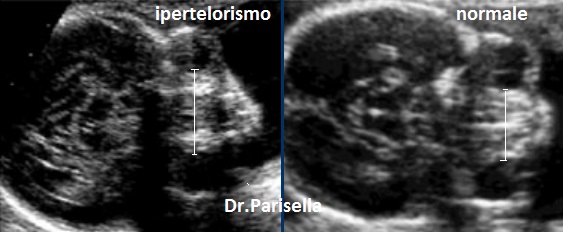

ipertelorismo

ipertelorismo